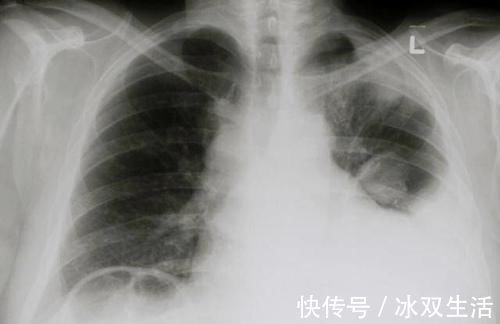

2、胸腔积液

胸腔积液同样也是癌症常见的一种严重并发症,这是由于发展到一定阶段之后,感染以及对局部组织的创伤会导致一部分液体始终存在于胸腔之中,尤其是肺癌的患者容易出现恶心的胸腔积液。在早期胸腔积液会导致患者呼吸短促,并且出现胸闷不适感。